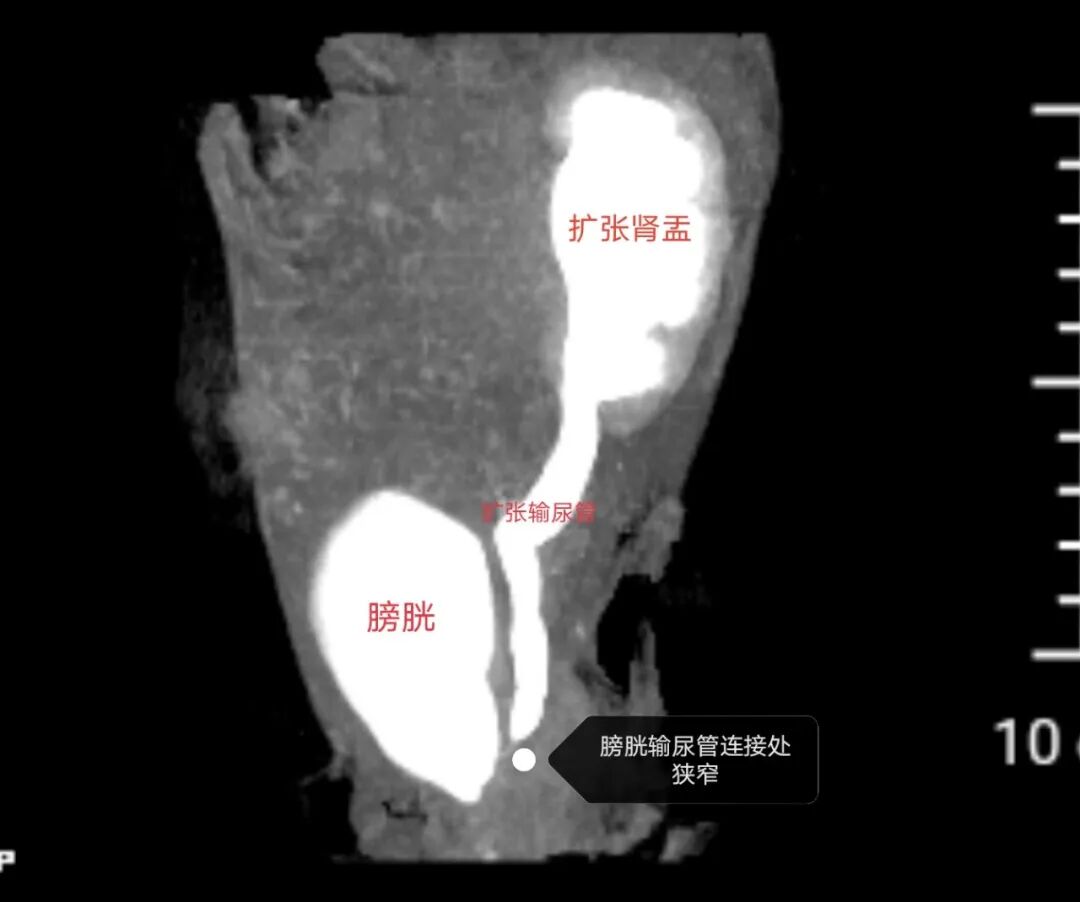

小儿外科主任胡东来耐心地对患儿家属解释:“尿路感染一定有原因,只有找到根源才能彻底解决问题。”经泌尿系CT检查,显示小尹还存在左侧膀胱输尿管连接处狭窄,导致左侧输尿管扩张,尿液引流不通畅,反复尿路感染,需要手术治疗。

术前泌尿系CT检查